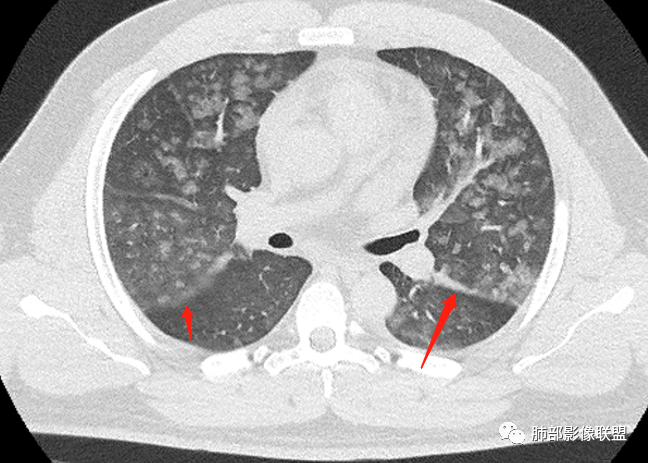

双肺多发弥漫性磨玻璃结节影,大小不一,形态不规则,部分融合,支气管未见明显扩张,部分血管束略增粗,叶裂胸膜增厚,临床有痛风,左足痛6天,考虑:1:痛风结节(一般实性结节,很少磨玻璃结节影)2:血管炎?3:病毒性肺炎(水痘-疱疹肺炎?)

双肺多发腺泡结节及磨玻璃,小叶间隔增厚(大网格状),腺泡结节内及磨玻璃内可见细网格影(小叶内间隔增厚),影像表现符合肺泡出血改变,血肌酐升高,考虑肺肾综合征。鉴别肺水肿。

年轻男性,既往血肌酐升高,左足痛六天入院,有痛风及高血压病史。CT示双肺多发磨玻璃结节影,不规则,部分融合成团或片状,小叶间隔增厚,以双下肺为明显,叶间胸膜亦见增厚。考虑为1.Good-Pasture综合征。2.病毒性肺炎?3.肺水肿?

年轻男性,痛风史,高血压史,肌酐高,左足痛6天入院。胸CT:双肺多发弥漫性磨玻璃结节影,大小不一,部分融合,上中下肺都有,中内带多,胸膜下少。部分血管束略增粗,小叶内间隔、小叶间隔增厚,下肺明显,左室大。叶裂胸膜增厚。临床有痛风,左足痛6天,考虑:心衰、间质性肺水肿?弥漫性肺泡出血?鉴别:MPA,肺肾综合征,痛风结节等。

多发GGO结节,边界清,以全小叶、小叶中心为主:

GGO背景

小叶间隔增厚,无明显重力趋势

少量积液,脂肪肝

这里有一点重力趋势

中轴间质稍增厚

细网格也明显

中轴间质增厚,小叶间隔增厚,小叶内间质增厚,部分重力作用,双侧对称,胸水,按理淋巴道回流受阻有

肺水肿类病变有

问题是腺泡结节如何解释?